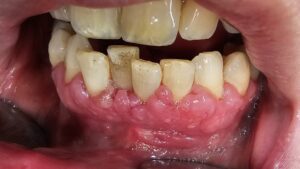

Zahnfleischtaschen sind kein eigenständiges Krankheitsbild, sondern das zentrale Merkmal einer Parodontitis. Sie entstehen, wenn die Entzündung den Zahnhalteapparat erreicht und Gewebe zerstört wird, das den Zahn im Kiefer verankert. Die Tiefe dieser Taschen – gemessen in Millimetern – ist der wichtigste Einzelwert, an dem Zahnärzte den Schweregrad einer Parodontitis festmachen und die Behandlung planen.

Jeder Zahn hat eine schmale Furche zwischen Zahnfleisch und Zahnoberfläche – den Sulkus. Das ist normal und gesund. Bei gesundem Zahnfleisch ist dieser Sulkus 1 bis 3 Millimeter tief. Das Zahnfleisch liegt straff am Zahn an, das darunterliegende Gewebe – Fasern, Knochen, Wurzelhaut – ist intakt. Die Zahnbürste erreicht den Sulkus, der Speichel spült ihn, das Immunsystem kontrolliert die wenigen Bakterien, die sich dort aufhalten.

Eine Zahnfleischtasche ist etwas grundlegend anderes. Sie entsteht nicht, weil der Sulkus „tiefer wird“, sondern weil die Verankerung des Zahnfleischs am Zahn zerstört wird. Die Fasern, die das Zahnfleisch am Zahn festhalten, lösen sich auf. Der Knochen darunter wird abgebaut. Es entsteht ein pathologischer Raum zwischen Zahnwurzel und Zahnfleisch, den keine Zahnbürste der Welt mehr erreicht.

Bei einer Gingivitis ist die Entzündung auf das Weichgewebe beschränkt. Das Zahnfleisch ist gerötet und geschwollen, aber der Zahnhalteapparat – Knochen, Fasern, Wurzelhaut – bleibt unversehrt. Wird die Plaque entfernt, heilt alles folgenlos aus.

4 Millimeter: die Grauzone. Hier beginnt es, behandlungsbedürftig zu werden. Eine 4-mm-Tasche kann bedeuten, dass der Knochenabbau gerade erst begonnen hat – oder dass das Zahnfleisch geschwollen ist und die Sondierungstiefe dadurch erhöht erscheint (→ Pseudotasche, siehe unten). Ob tatsächlich Knochen verloren gegangen ist, zeigt erst das Röntgenbild. In jedem Fall gilt: Eine 4-mm-Tasche ist ein Warnsignal, aber kein Grund zur Panik. Mit konsequenter Behandlung und guter Mundhygiene lassen sich die Werte in vielen Fällen wieder verbessern.

5 bis 6 Millimeter: moderate Parodontitis. Hier ist in der Regel bereits Knochen verloren gegangen. Die Tasche reicht tiefer als jede Zahnbürste, und auch Zahnseide oder Interdentalbürsten erreichen den Taschenboden nicht mehr. Diese Taschen müssen professionell behandelt werden – in der Regel durch subgingivale Reinigung der Wurzeloberflächen (Scaling and Root Planing). Die gute Nachricht: Bei konsequenter Therapie können Taschentiefen von 5 bis 6 Millimetern oft um 1 bis 2 Millimeter reduziert werden.

7 Millimeter und mehr: schwere Parodontitis. Hier ist der Knochenabbau deutlich fortgeschritten. Taschen dieser Tiefe sind mit geschlossener Behandlung allein häufig nicht ausreichend beherrschbar. Oft ist eine chirurgische Behandlung – eine sogenannte Lappen-OP – notwendig, um unter Sicht arbeiten zu können. Trotzdem: Auch bei tiefen Taschen ist der Zahn nicht verloren. Die Behandlung ist aufwendiger, die Prognose hängt stärker von Mitarbeit und Nachsorge ab – aber Zahnerhalt ist in vielen Fällen möglich.